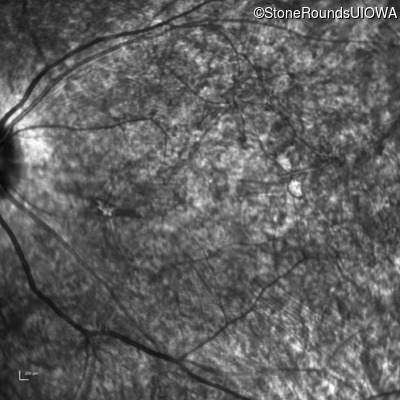

Infrared Fundus Photograph - Left - 20/250 sc

Exemplar